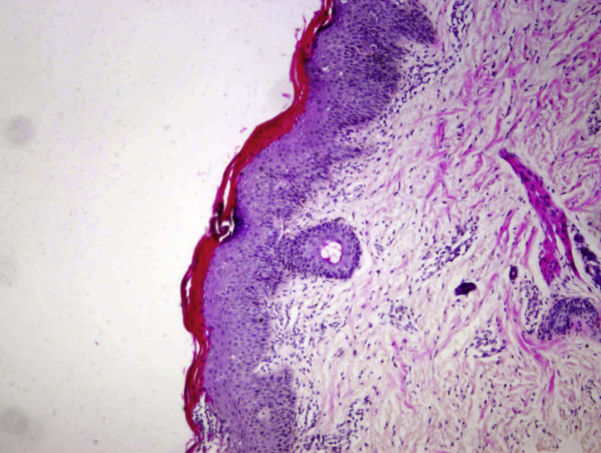

Histologic examination found marked hyperkeratosis and parakeratosis, a reduced to absent stratum granulosum, and a moderate amount of acanthosis of the epidermis (Fig 2).

Fig 2.

Histopathologic examination (hematoxylin-eosin stain) shows psoriasiform dermatitis with acanthosis, zones of parakeratosis, and an exocytosis of neutrophils.